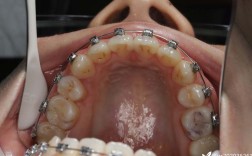

在口腔正畸与颌面外科领域,正颌手术前的正畸治疗(简称“术前正畸”)是骨性错颌畸形矫正的重要环节,其核心目的是通过移动牙齿、调整咬合关系,为颌骨手术创造条件,但临床上常有患者疑问:“不做术前正畸是否可以?”这一问题需结合畸形类型、严重程度、手术方式及患者需求综合判断,不能一概而论。

- 去除牙齿代偿性倾斜:骨性畸形常伴随牙齿代偿(如“地包天”患者上前牙过度唇倾、“龅牙”患者上前牙过度舌倾),术前需将牙齿移动至骨骼基座内的正常位置,避免术后牙齿与颌骨不匹配,降低复发风险。

- 建立稳定咬合关系:通过排齐牙列、调整 Spee 曲线、纠正中线偏斜等,确保术后上下颌牙齿尖窝交错、咬合力分布均匀,避免术后咬合紊乱或颞下颌关节问题。